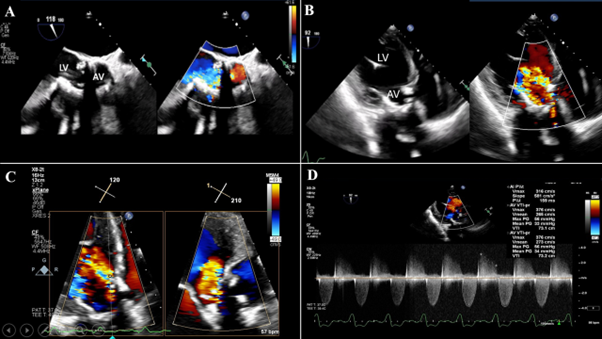

📝 Want to know contemporary & future options for the management of severe 2ndary MR? Check out this new JCF SotA Review to learn about TEER & emerging transcatheter MV repair & replacement devices here! 🔗bit.ly/4fbGuKY